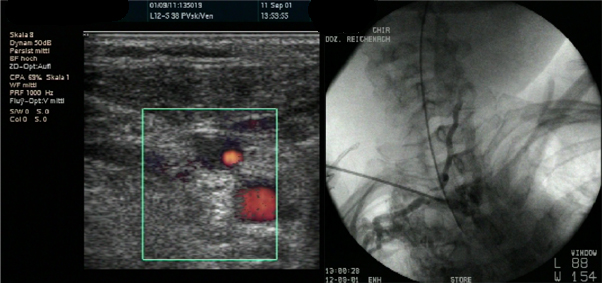

Goldstandard ist die Punktion der rechten Vena jugularis/anonyma supraklavikulär nach oder unter sonographischer Kontrolle. Die Sonographie muß Lagevarietäten klären und Thrombosen nach früherer Katheterisierung ausschließen.

Die Vena jugularis/ Vena anonyma kann nach Yoffa zwischen medialem und lateralem Kopf des Musculus sternocleidomastoideus von ventral punktiert werden oder horizontal von lateral. Diese Methode wurde 1972 von den amerikanischen Herzchirurgen Garcia, Mispireta und Pinho nach ausführlichen anatomischen Präparationen als einfachster und ungefährlichster Zugang beschrieben. Das Zielgebiet, der Zusammenfluß von Vena jugularis und Vena subclavia zur Vena anonyma ist so groß, dass die Punktion auch ohne Sonographie immer beim ersten Stich gelingt.

Die Punktion von ventral kann unter realtime Sonographie mit einem Standardschallkopf wegen des geringen Abstands zur Clavicula nur in der kurzen Schallachse erfolgen, wobei die Nadel nur abschnittsweise sichtbar ist. Mit dem kleinen 22 MHz Fingerschallkopf aus der Rheumatologie ist auch eine Punktion in der langen Schallachse möglich.